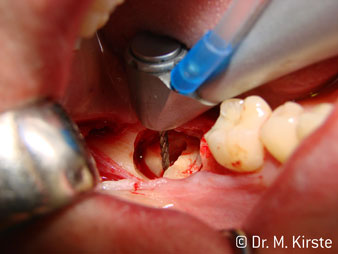

45° açılı angldruva geniş avantaj yelpazesi sebebiyle özellikle seçildi. Bu enstrümanın geliştirilme nedeni olan cerrah meslektaşlarım angldruvaların kısıtlı alanlardaki çalışma yeteneğini yakında takdir edeceklerdir. Özellikle gömük diş çekimlerinde (res. 2) yumuşak dokunun yanak bölgesine doğru yarılmasına gerek kalmaz(res. 3). Angldruvanın kafa dizaynı sayesinde retromolar bölgede hızlı ve güvenli çalışma sağlar.

Hızlı çalışmadan bahsetmişken: angldruva, 100,000 rpm üzerinde çalışırken aynı anda profesyonel bir soğutma sağlanır

Angldruva kafası içindeki profesyonel tasarımlı dişliler frezin sessiz çalışmasını garanti eder; kök separasyonu yapılırken atravmatik operasyona olanak verir. (res. 4-9).